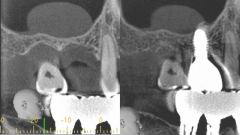

パッチテクニック症例1

治療前

治療前 治療後

治療後

◆治療内容

歯周病で失われた歯肉や歯槽骨などの歯周組織を罹患前の状態にまで改善できます。 歯槽骨の再生とともに歯根膜空隙も再生された例も確認されています。

◆リスク

・感染リスクが高まる

・瘢痕による審美性の悪化

◆治療費

保険適用外 50,000円 (税別)